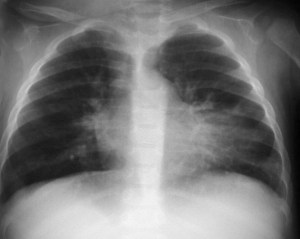

SIGNO DE LA ALTERACIÓN DEL CONTORNO AÓRTICO

La irregularidad, abombamiento o borramiento del arco aórtico en la radiografía de tórax en bipedestación o en decúbito supino, en un paciente con traumatismo torácico, obliga a descartar rotura aórtica como causa de dicha alteración. La flecha muestra el contorno aórtico anómalo. Además, hay un aumento de densidad en el hemitórax izquierdo correspondiente a derrame pleural –hemotórax en este caso-, que refuerza la sospecha de rotura aórtica.